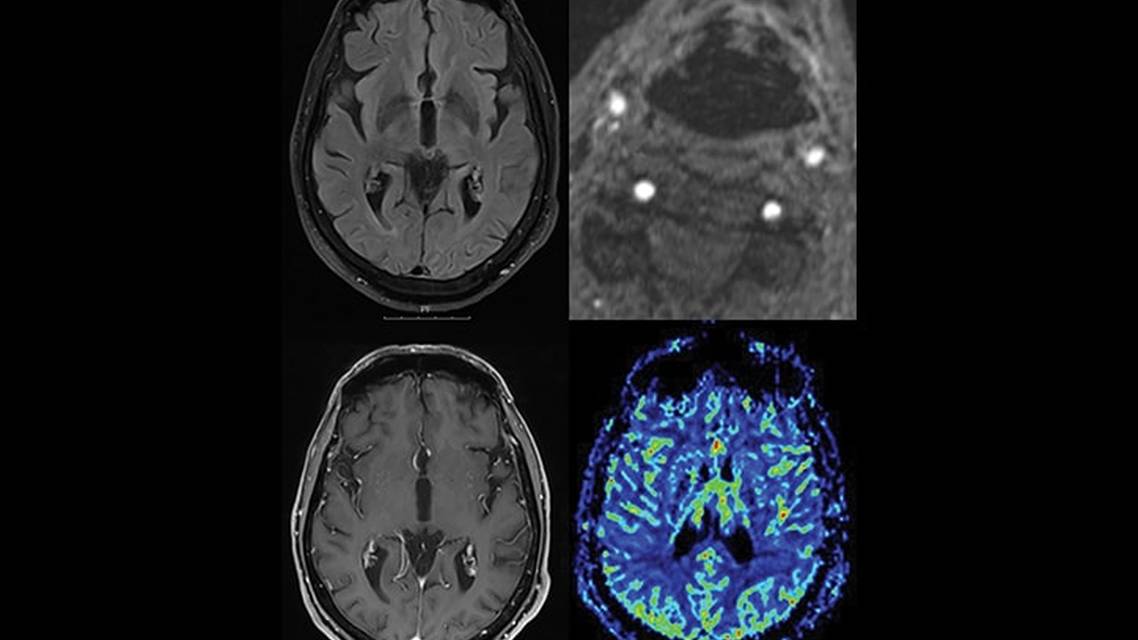

Laboratory workup results were unremarkable (Table), and there were no parenchymal changes evident on brain MRI (Figure 1A). A magnetic resonance angiographic study, however, revealed a left internal carotid artery (ICA) occlusion and a right ICA critical stenosis (Figure 1B). Perfusion studies showed global and symmetric hypoperfusion (Figure 1D), and Doppler ultrasound revealed bilateral dampened middle cerebral artery (MCA) velocities.

Figure 1. Axial T2-weighted fluid-attenuated inversion recovery image shows no basal ganglia structural lesions (A). Magnetic resonance angiography demonstrates right internal carotid artery critical stenosis (white arrow) and absence of left internal carotid artery blood flow signal (yellow arrow) (B). Axial postgadolinium T1-weighted image shows no enhancing lesions that could suggest brain metastases (C). Cerebral blood flow demonstrates global brain hypoperfusion (D).